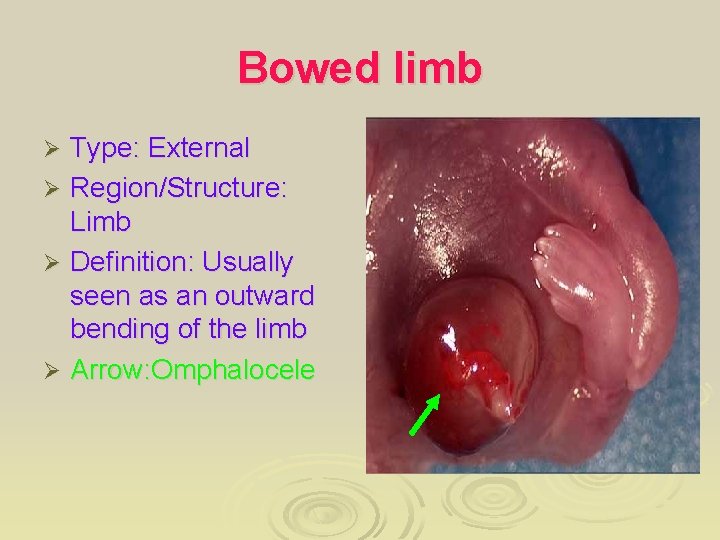

Bowed limb Type: External Ø Region/Structure: Limb Ø Definition: Usually seen as an outward bending of the limb Ø Arrow: Omphalocele Ø